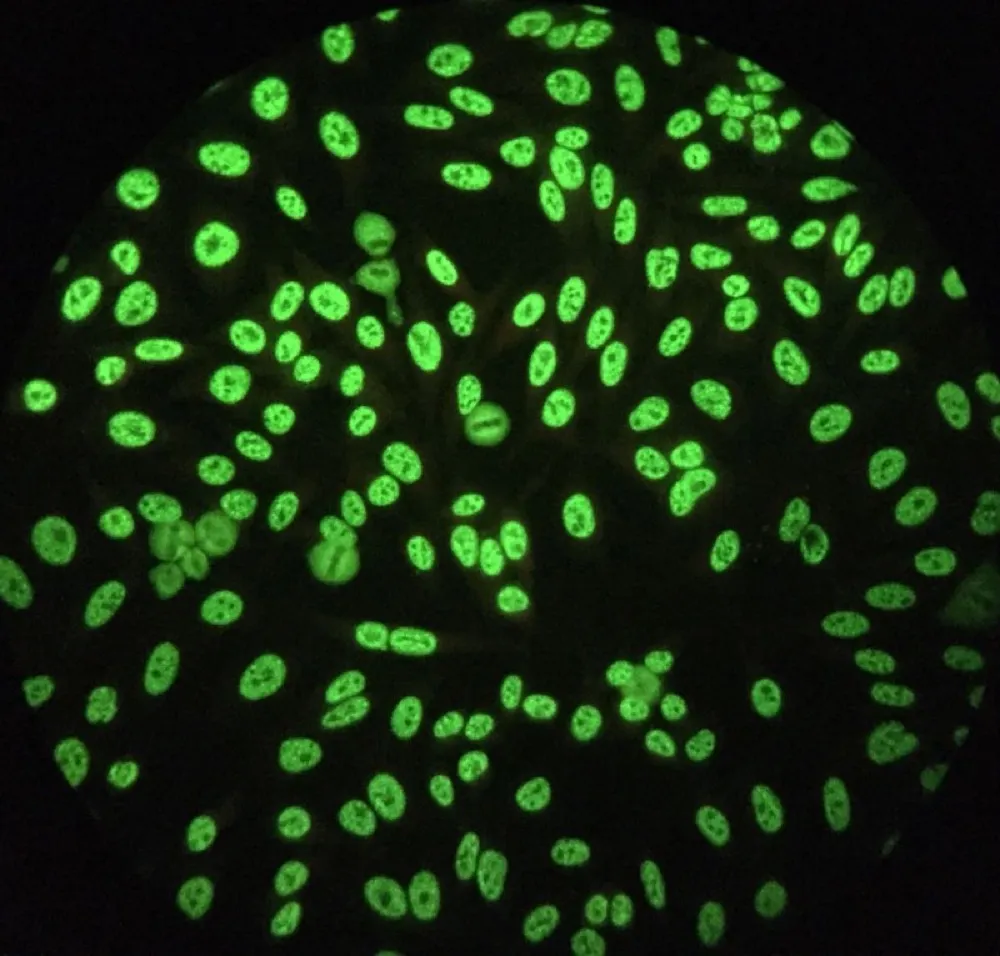

Necrose cortical renal, uma causa subdiagnosticada de IRA

Necrose cortical renal, uma causa subdiagnosticada de IRA

Frequentemente nos deparamos com pacientes que evoluem com quadro de IRA "desproporcional" ao quadro séptico, necrose cortical renal é uma entidade que não pode ser esquecida, principalmente em pacientes com complicações obstétricas